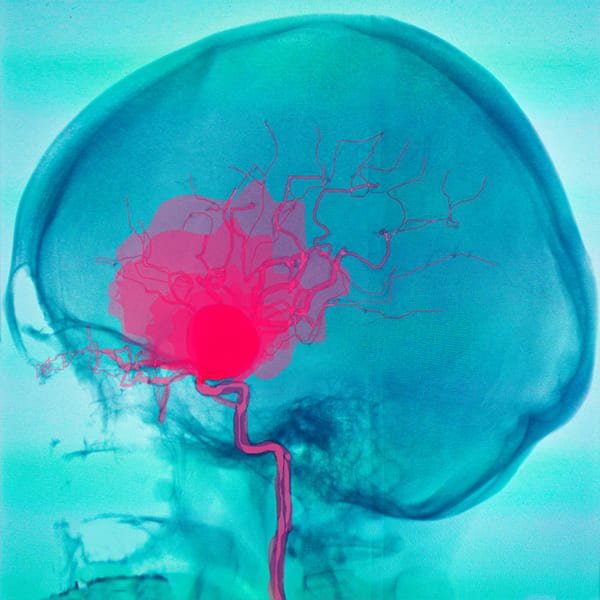

Cirugía aneurisma cerebral

Reparación de la zona débil en la pared de un vaso sanguíneo.